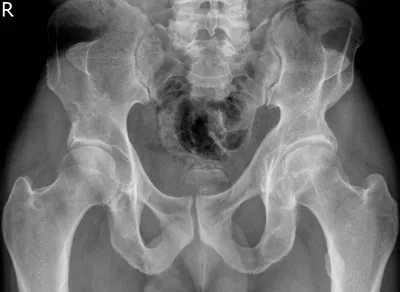

Dysplasia Radiology Images

Browse 5 medical images tagged with dysplasia. This collection includes various imaging modalities for medical education and reference.

- This collection contains 5 radiology images related to dysplasia, including various imaging modalities such as X-rays, MRIs, CT scans, and ultrasound images commonly used in medical diagnosis and education.